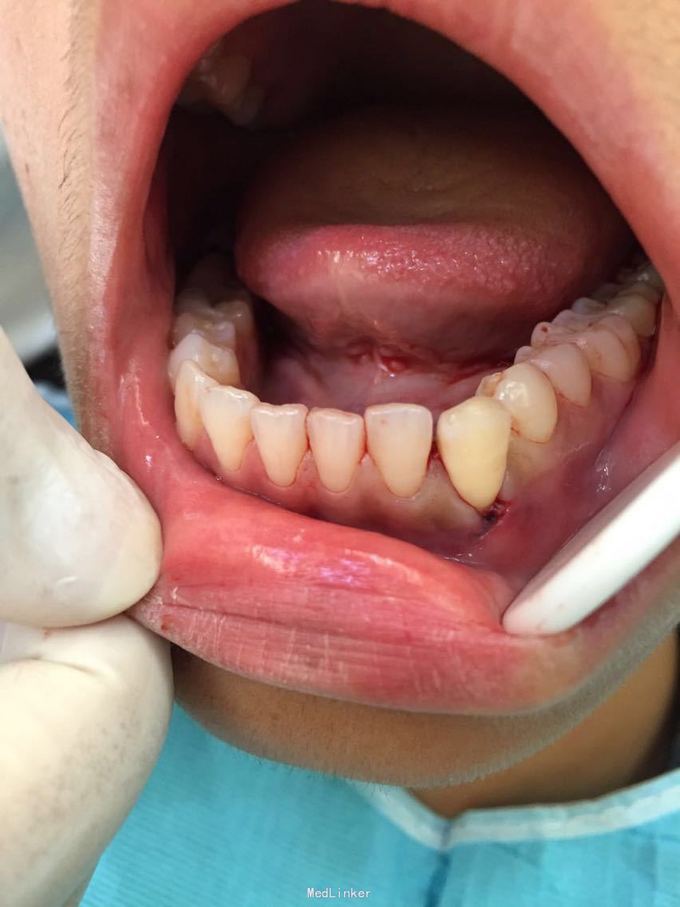

D3牙脱位 D3体外根管治疗后垫底充填,盐水和双氧水浸泡后,刮尽牙根的牙周膜后放置盐水和庆大霉素液中15分钟。局麻下刮除牙槽窝内血凝块至流鲜血后盐水和庆大霉素交替冲洗,明胶海绵拭干牙槽窝,浸泡好的牙体植入牙槽窝内并复位,舌侧树脂牙周夹板固定D123456,牙周上派丽奥。随诊

1天后复诊,3天后复诊,7天后复诊,一个月后复诊,3个月后复诊。1个半月后复诊未发现牙周有较大吸收和炎症感染。